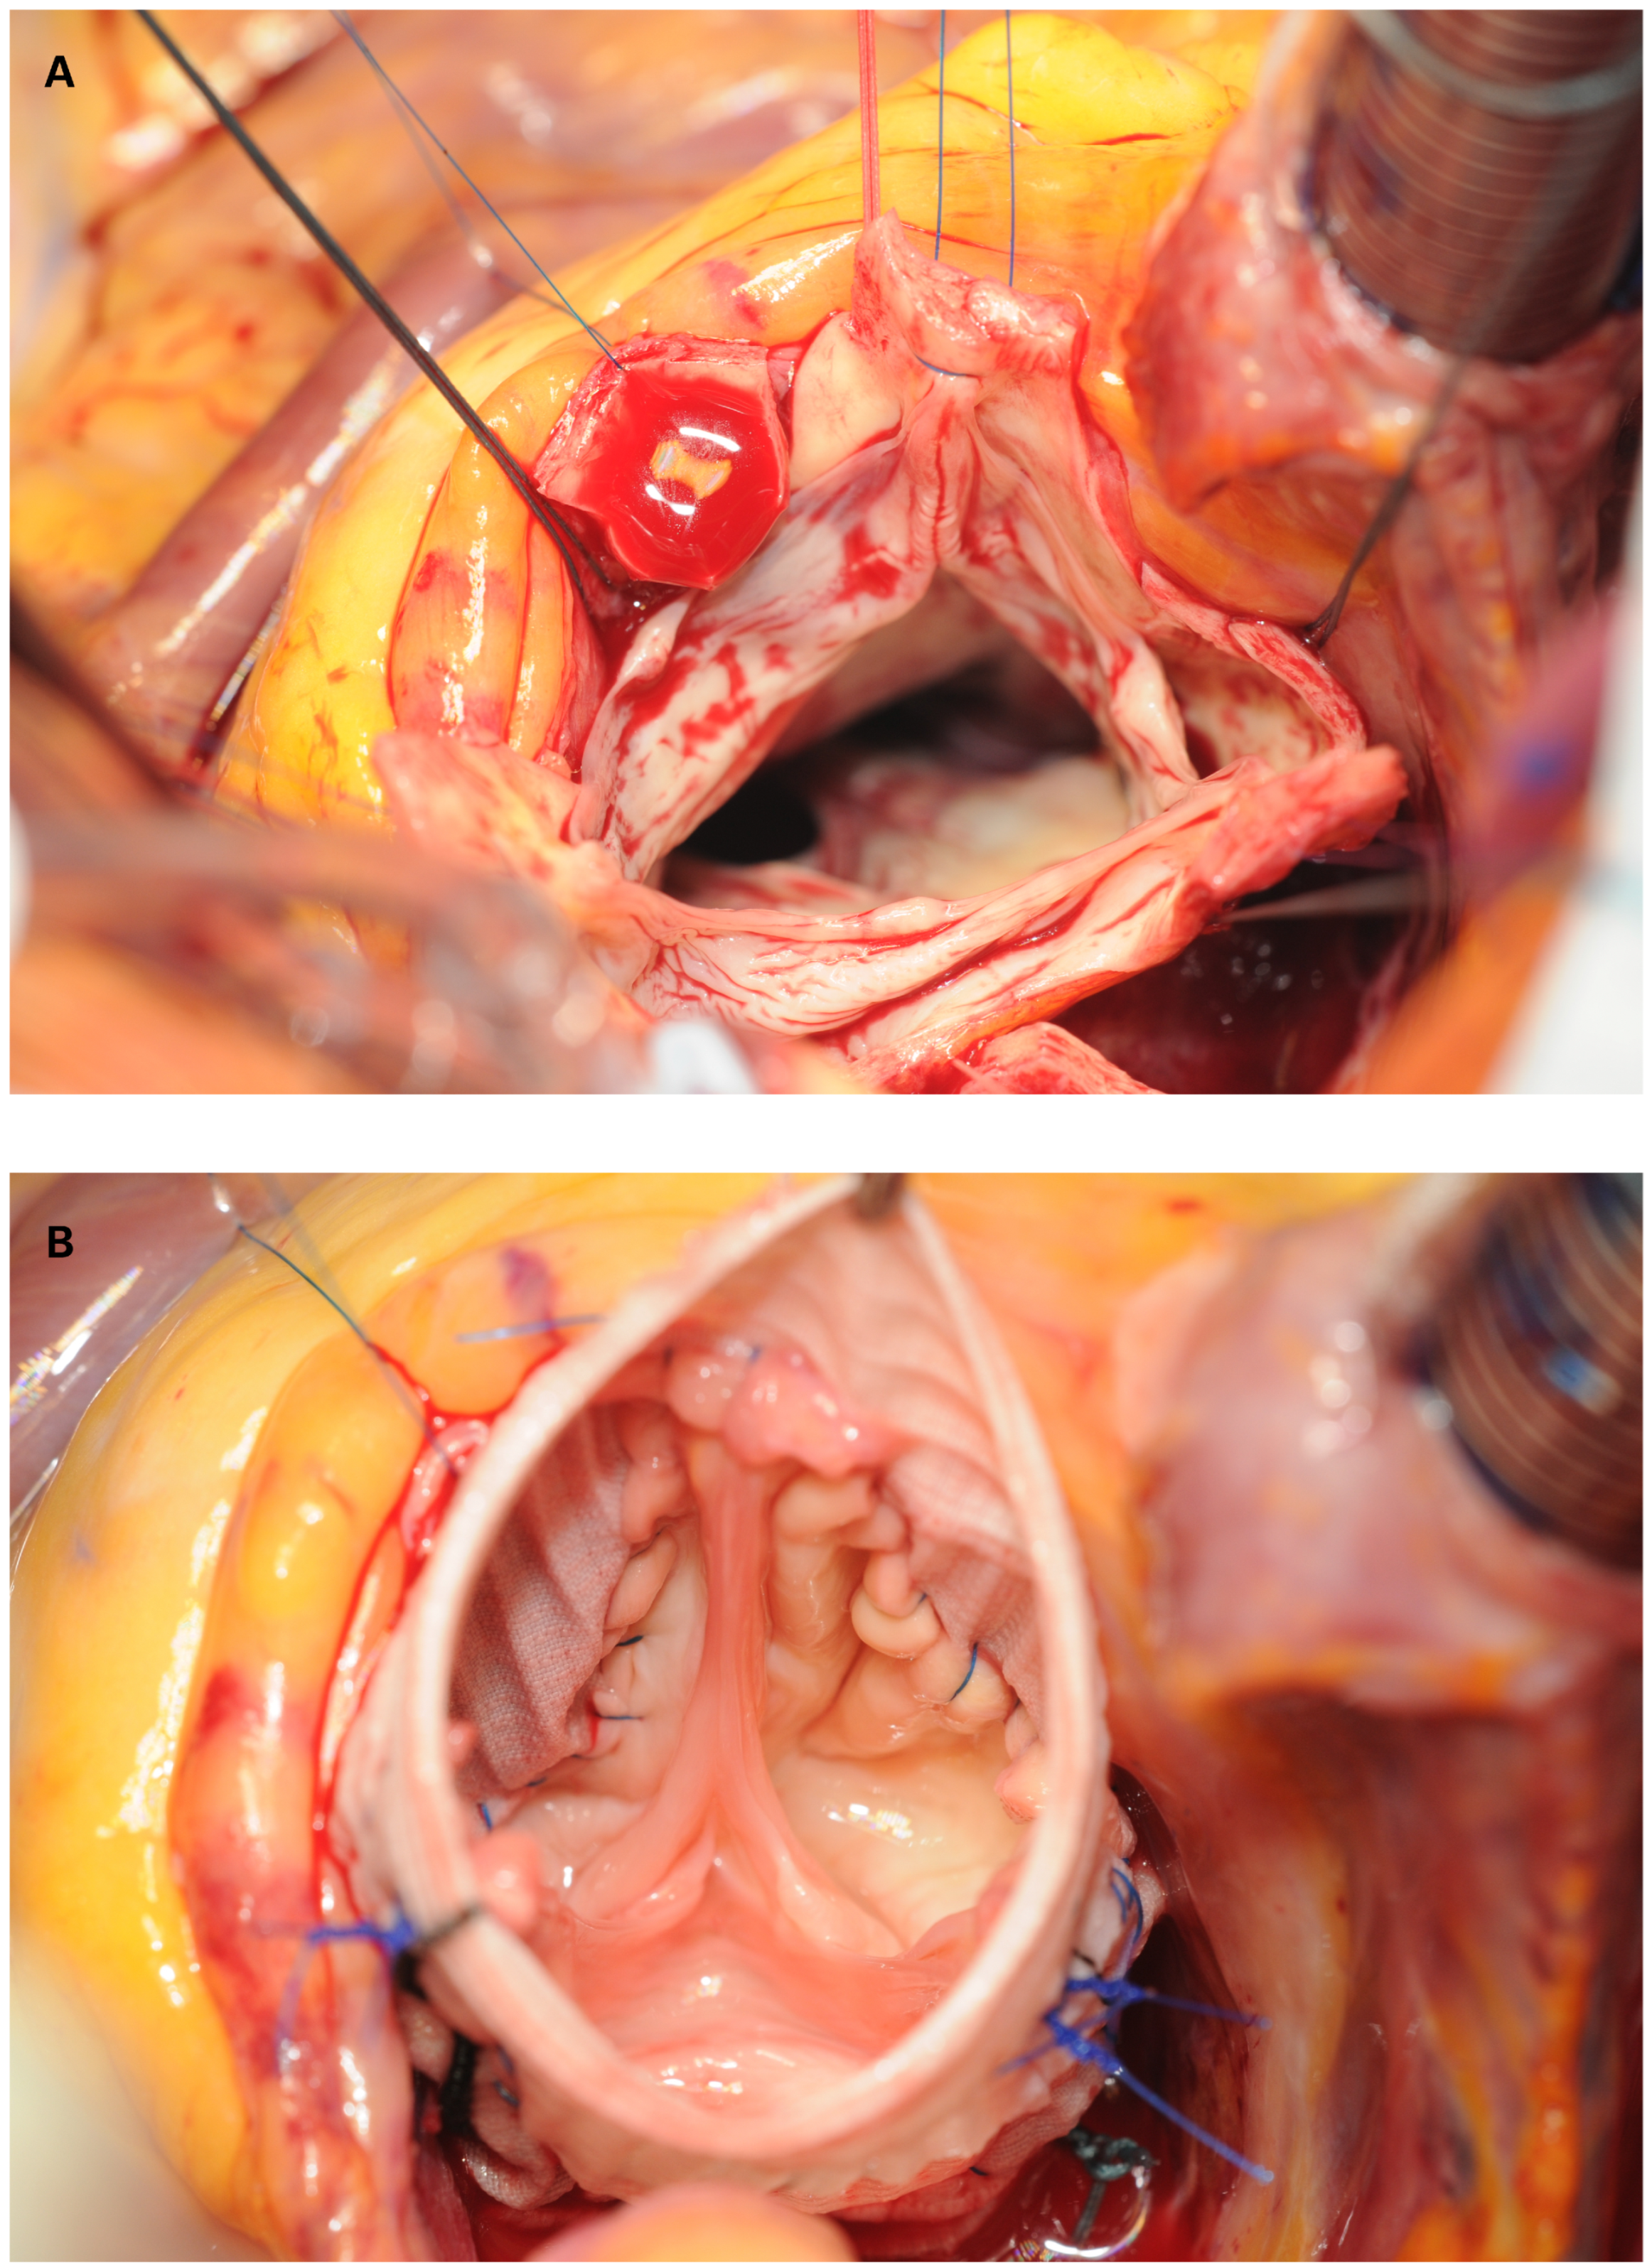

Figure 4. Intraoperative view of an aortic valve sparing root replacement: a: situs after complete resection of the aortic wall with the tricuspid valve being spared b: following reimplantation of the aortic valve and small plication of one aortic leaflet.

Composite graft replacement of the aortic root (called the Bentall procedure in the past) is the most radical treatment to eradicate pathologies of the aortic root with or without involvement of the aortic valve. This procedure has helped to save a tremendous number of lives and has received important technical refinements that have resulted in a significant reduction of perioperative morbidity and mortality in the last 20 years [10,11,12,13,14,15,16,17,18,19]. Beside modifications of the original technique (such as the open technique that allows for instance a better visual control during coronary reimplantation), optimisation of cardiopulmonary bypass technology and improved myocardial protection together with better perioperative management have contributed to make the electively performed composite graft procedure a standard of practice with very low mortality and morbidity in high volume centres. Parallel to this, technical advances have also increasingly allowed the native aortic valve to be preserved in a substantial number of patients (remodelling or re-implantation procedures as shown in Figure 4), thus avoiding the implantation of a prosthetic valve and life-long anticoagulation, which is particularly beneficial in younger patients [20,21,22,23].